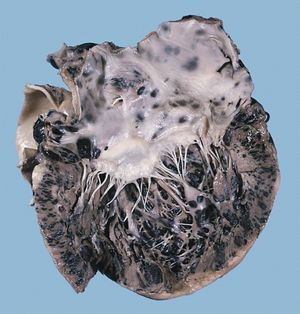

호르몬은 일부 암의 세포 생장을 촉진시켜 암 발달에 기여한다.[142] 인슐린 유사 성장 인자와 결합 단백질은 암 세포의 성장, 분화, 세포자살에 중요한 역할을 하며, 발암에도 영향을 줄 수 있다.[143]호르몬은 유방암, 자궁내막암, 전립선암, 난소암, 정소암 등 성 관련 암과 갑상선암 및 골종양에서 중요한 전달자 역할을 한다.[142] 예를 들어 유방암이 있는 여성의 딸은 에스트로겐과 프로게스테론 농도가 높아 유방암 발생률이 높게 나타나며, 이는 호르몬과 유방암 발생 간의 관련성을 시사한다.[142] 아프리카 남성은 테스토스테론 농도가 높아 전립선암 발병률이 높고, 아시아 남성은 테스토스테론 활성화 물질 농도가 낮아 전립선암 발병률이 낮다.[142] 호르몬 대체요법을 받는 여성은 호르몬 관련 암 발생 가능성이 높으며, 성장 호르몬은 골육종을 촉진하기도 한다.[142] 암 치료 방법 중에는 호르몬 수치를 낮춰 종양 성장을 억제하거나 암 세포 자살을 유도하는 방법도 있다.[142]

연구 결과에 따르면, 염증은 암 발생 및 발달에 영향을 미친다.[155] 만성 염증은 DNA 손상을 누적시켜 돌연변이를 유발하고,[156] 종양 주변 환경에 영향을 주어 암 세포 확산, 생존, 혈관 형성, 전이를 촉진한다.[157] 염증성 장질환 환자는 대장암 발생 가능성이 높다.[97]

장기 이식으로 인해 종양이 발달하는 경우는 드물지만, 이식 당시 발견되지 않은 흑색종이 원인으로 작용할 수 있다.[165][81] 바이러스 감염 장기 세포가 이식 후 종양으로 발달하여 카포시육종을 유발한 사례도 보고되었다.[166][82]